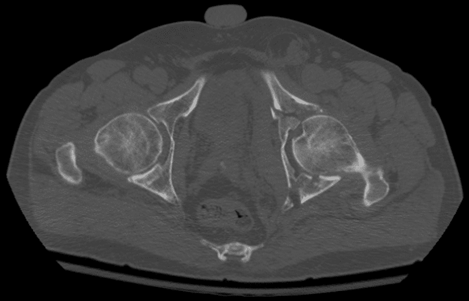

إلا أن التصوير المقطعي CT هو المعيار الذهبي للتشخيص، إذ يحدد نمط الكسر وامتداده بدقة ويُستخدم لتخطيط العلاج الجراحي.

التصنيف

يعتمد التصنيف الأكثر شيوعًا وهو Judet & Letournel على تقسيم الكسور إلى: